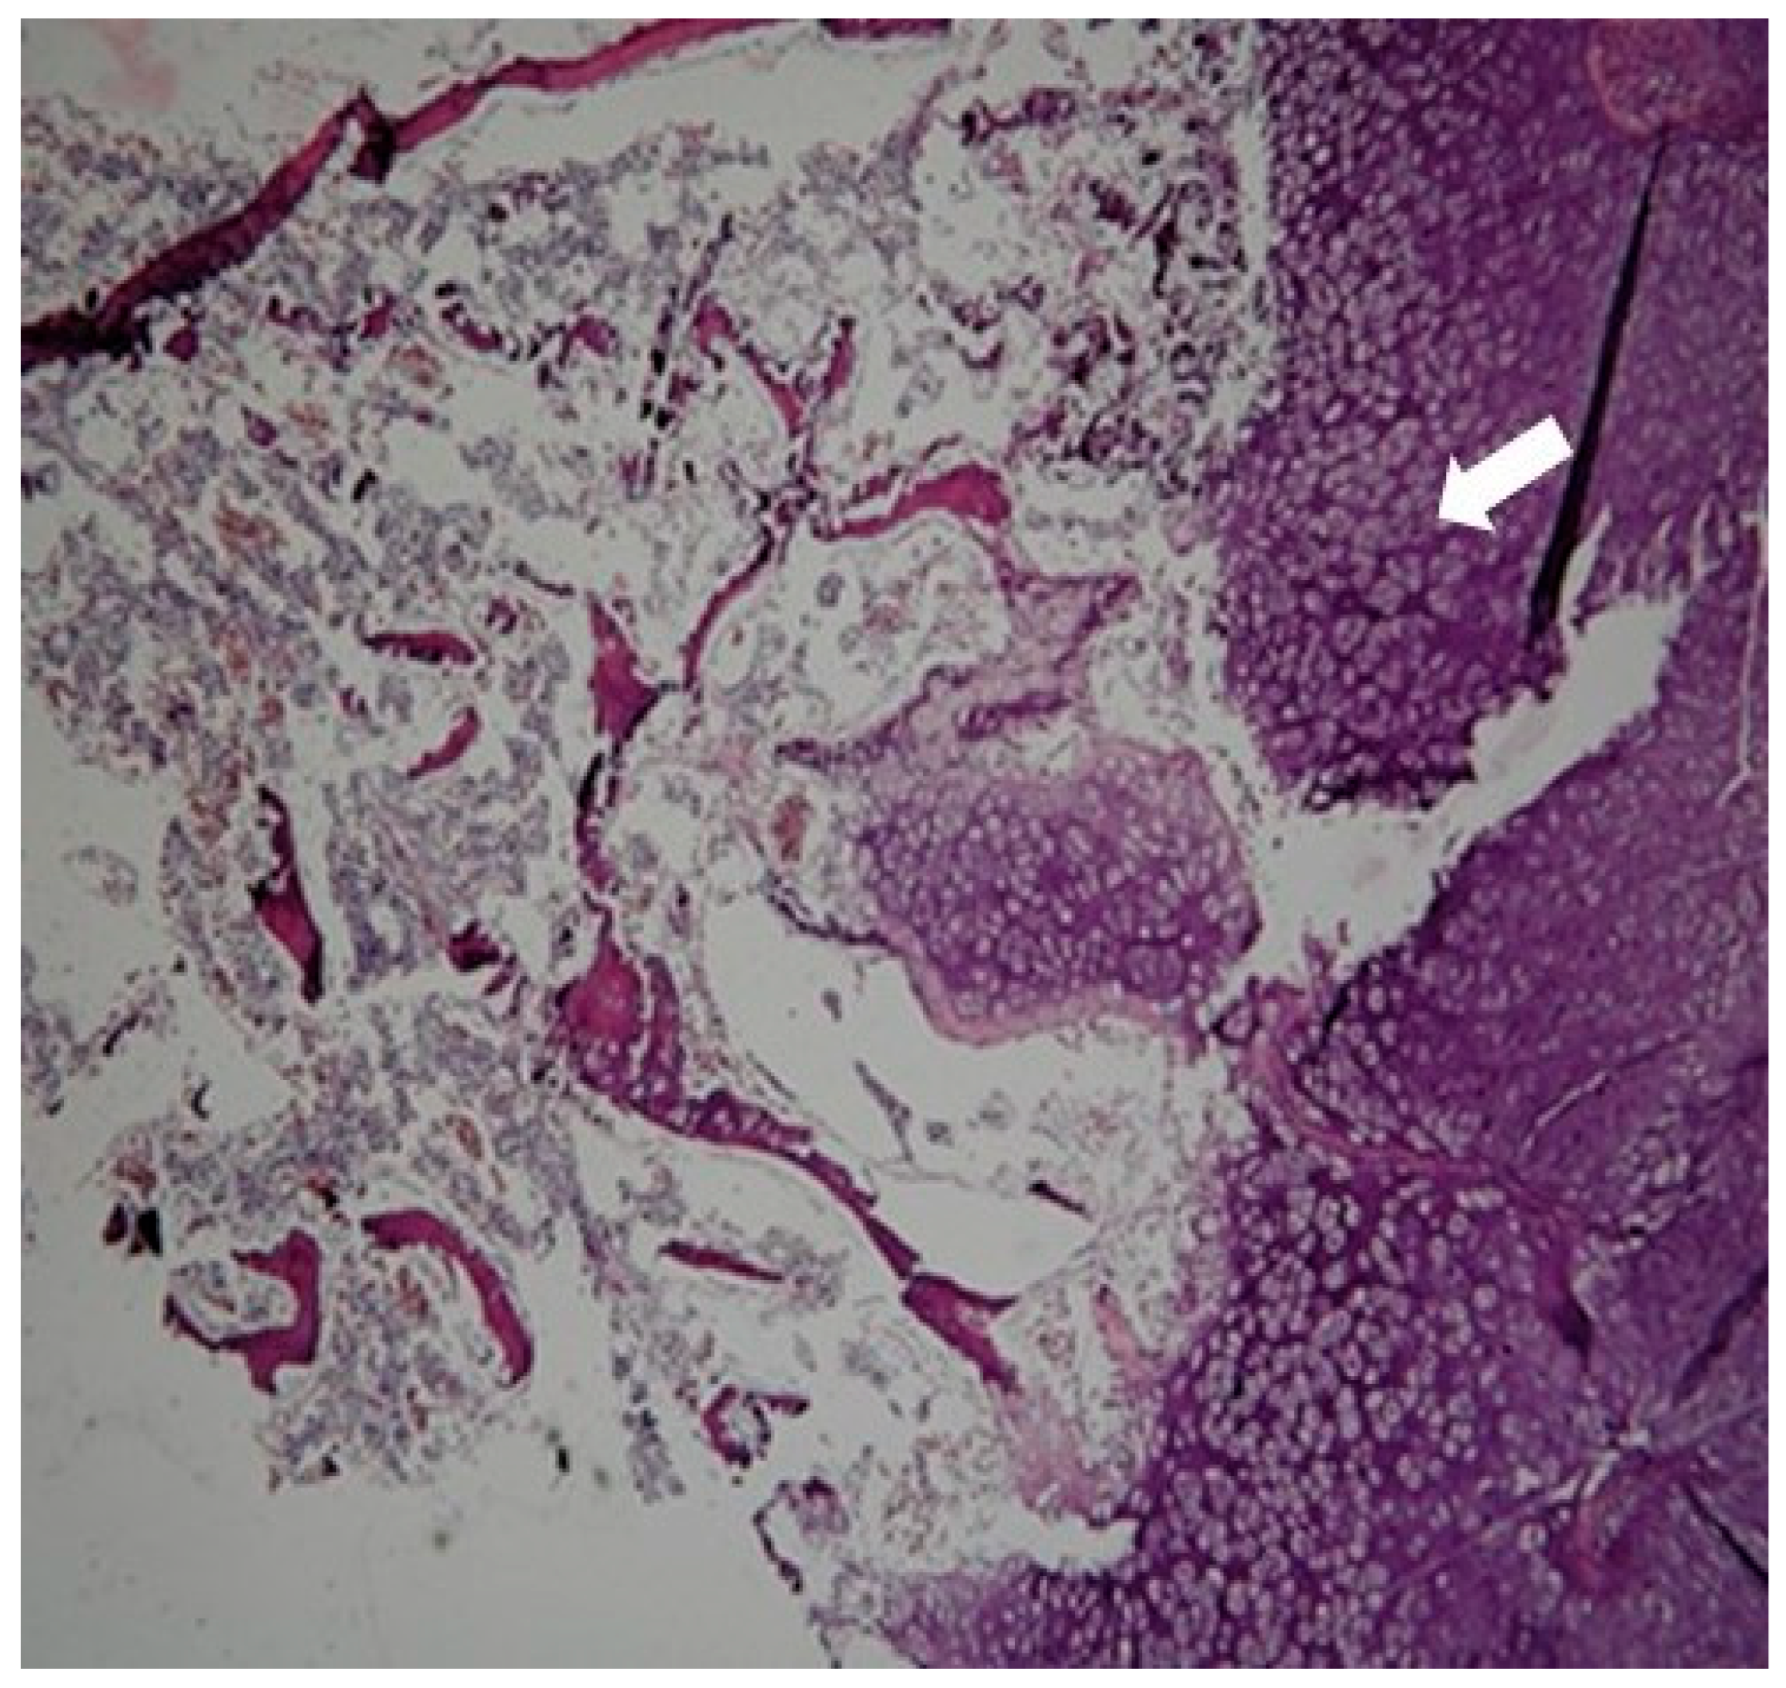

2. Case Presentation